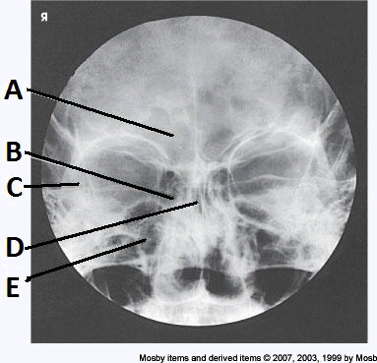

4. Examine the image of the paranasal sinuses below. The letter D labels the:

a. maxillary sinuses

b. ethmoid sinuses

c. sphenoid sinuses

d. frontal sinuses

__ 7. Examine the image of the paranasal sinuses below. The letter B labels the:

a. ethmoid sinuses

b. sphenoid sinuses

c. maxillary sinuses